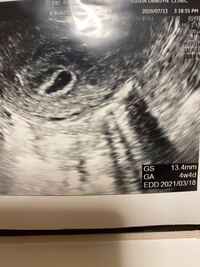

6w1d 心拍 確認-胎嚢確認からちょうど一週間後、心拍確認に行きました。 移植日から見ると6w1d、前回の胎嚢の大きさから行くと6w3dくらいです。 まずは忘れずに、前回渡されていたMedical Recordの公開同意書を提出。 BOGYNに今までの治療歴を送って貰います。 心拍確認も今まで通り経腟エコーで。妊娠週 6w1d 排卵日が特定できているので、確実に6w1dのエコーです (^^)元気な心拍と2mmの赤ちゃんが確認できました! 2人目の妊娠なので、まだ1歳10ヶ月の長男を抱っこしたり追いかけ回したりでゆっくりできないので、赤ちゃんが心配ですが生命力を信じて

体外受精で5w0dに胎嚢(8mm)確認出来てます。 本日6w1d。胎嚢14mm。胎芽2mm。心拍確認済(エコーで拡大して分かる程度) 先生に「赤ちゃん小さいな〜〜」とボソリと言われました。 また、妊娠判定日がBT11でHCG500半ば。 6w1d 心拍確認出来ませんでした 不安になってしまい、また質問させて下さい。 今までの経過は 4w2d胎嚢2mm確認 5w1d胎嚢8mm確認 6w1d胎嚢199mmと卵黄嚢確認 となっています。 ちなみに週数は最終生理から数えてで、医師から告げられたものではありません。 心拍は何週目に確認できましたか? 妊娠初期の妊娠の大まかな目安は8週までに胎児心拍が認められることです。 そのため、 妊娠検薬で早めに妊娠がわかったとしても、 その後心拍確認まで何度も病院に足を運ぶことになります。 およそ1週間ごとに診察